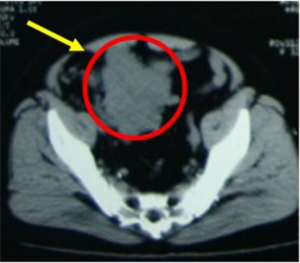

Ca lâm sàng: Ung thư đại tràng ở bệnh nhân 15 tuổi

GS.TS Mai Trọng Khoa; BSNT Hoàng Mạnh Đức, Ths Bùi Quang Lộc , PGS.TS Phạm Cẩm Phương, Bsck II Hoàng Anh, Trung tâm y học hạt nhân và ung bướu, bệnh viện Bạch Mai Đại học Y Hà Nội Trung tâm cấp cứu A9, bệnh viện Bạch Mai Ung thư...